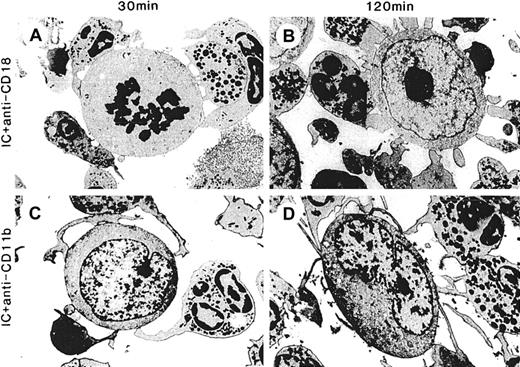

Effect of function-blocking mAbs against Mac-1 (CD11b/CD18) on spreading, adhesion, and cytolysis by PMN with hu14.18/GM-CSF.

ADCC with hu14.18/GM-CSF was as described in Figure 3 except that function-blocking mAbs were added just before the addition of hu14.18/GM-CSF. ADCC was performed in the presence of anti-CD18 7E4mAb (10 μg/mL) for (A) 30 minutes and (B) 120 minutes or anti-CD11b 2LPM19C mAb (10 μg/mL) for (C) 30 minutes and (D) 120 minutes. Electron micrographs were taken with an original magnification of × 5400.